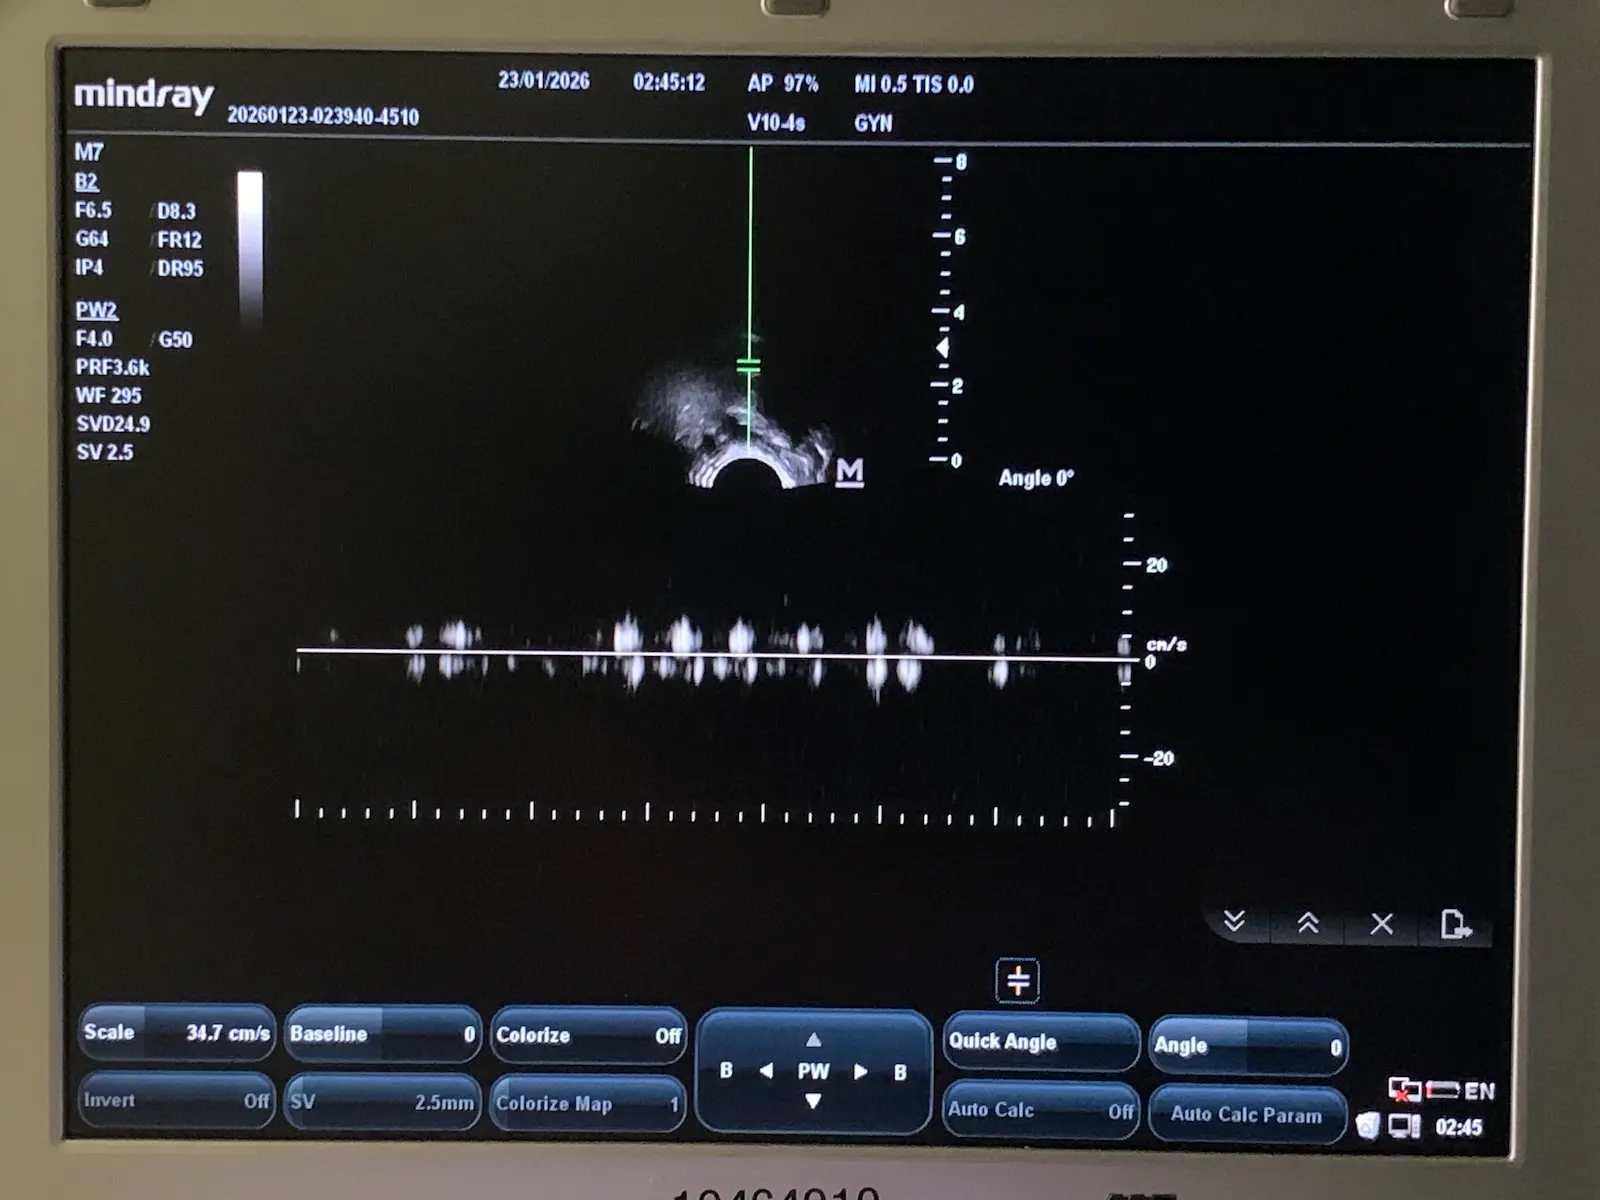

Condition: Used, working

Brand: Mindray

Model: V10-4s

MPN: 023-000041-00

Probe Type: Endocavity / Transvaginal / Micro-convex

Frequency Range: 4.0 MHz – 10.0 MHz

Compatibility: Mindray M7, M7 Premium, M7 Expert, M6 series

Applications: OB/GYN, Urology, Veterinary

Up for sale is a genuine Mindray V10-4s curved array endocavity probe. This transducer is designed for high-resolution imaging in obstetrics, gynecology, and urology. It features a wide-band frequency range (4–10 MHz) and a small 10mm radius for patient comfort.

Source: Removed from a clinical environment. The probe was tested on a Mindray MR-M7 Ultrasound unit to confirm full functionality, image quality, and connectivity.